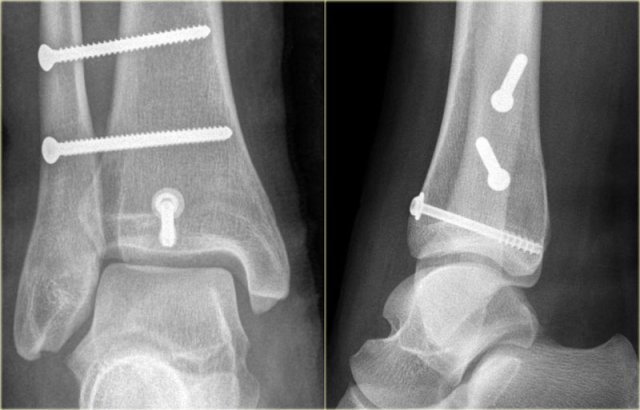

In some cases a fracture of the posterior malleolus is barely or not visible on the radiographs and can only be seen on CT.

First study the radiographs and then continue with the CT.

By the way....there are two fractures.

The CT shows an avulsion of the tertius at the insertion of the posterior syndesmosis (red arrows).

The alignment is so perfect, that you do not see the fracture on the radiographs.

Maybe the fracture is seen on the AP-view as indicated by the red arrows, but this is questionable.

Notice that there is also an avulsion at the tibial insertion of the anterior syndesmosis, i.e. Tillaux fracture.

This combination of findings implicate that the ankle is unstable.

A syndesmotic screw has to be inserted.